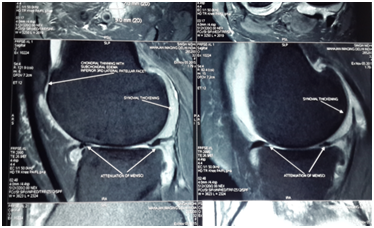

Biochemical test showed decreased level of ESR, CRP and Rheumatoid Titer. X-rays showed less Osteopenia. MRI of knee showed increased thickness in articular cartilage with reduction in synovial thickening and joint effusion. There was visible repair of articular cartilage breach Figures (4-6B).

Figure 4 (B) Post-stemcell transplantation.

Figure 5 (B) Post-stemcell transplantation.

Figure 6 (A) Pre-stemcell transplantation.

Figure 6 (B) Post stemcell transplantation.